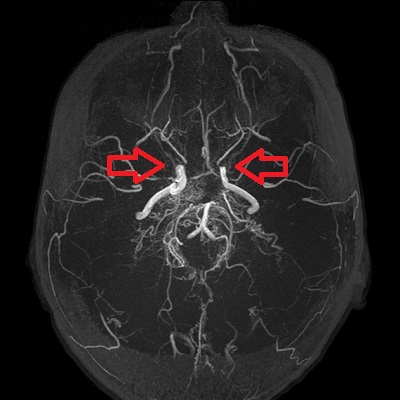

- 類もやもや病(ウィリス動脈輪閉塞症)

特に原因のはっきりしない「もやもや病(ウィリス動脈輪閉塞症)」は、内頸動脈末端と前中大脳動脈部が狭窄・ 閉塞し、基底角部の異常血管網(もやもや血管)が発達する謎の病気です。

甲状腺機能亢進症/バセドウ病など基礎疾患がある場合、「類もやもや病」と言われ、甲状腺治療開始後に脳虚血症状も改善する報告が多くあります。状況によっては(改善が見込めない場合)、甲状腺機能改善後に脳神経外科で脳血行再建術を行う事になります。